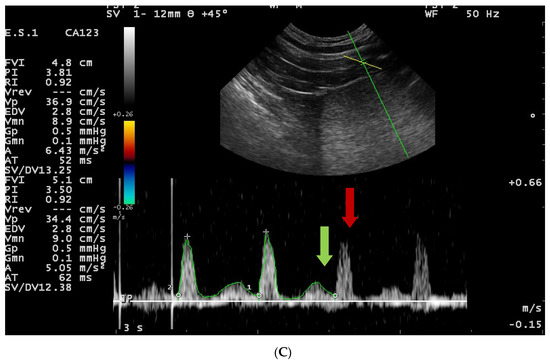

2.6. Doppler Ultrasonography—Testes

3.4. Doppler Ultrasonography of the Testicular Artery